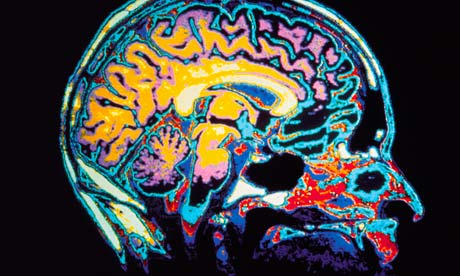

أول زراعة لجهاز في دماغ مريض بالزهايمر يحفز الذاكرة

ذكرت وسائل إعلام أميركية أن الباحثين في مركز جون هوبكينز الطبي أجروا في نوفمبر الماضي أول عملية زرع جهاز في دماغ مريض يعاني مرض الزهايمر في بداية مراحله، يساعد على تحفيز الذاكرة وعكس التراجع المعرفي الناجم عن المرض. وقال الباحثون في المركز إن الجراحة هي جزء من تجربة سريرية تدشّن اتجاهاً جديداً في البحث السريري وتهدف إلى إبطاء أو وقف الدمار الناجم عن الأمراض التي تسرق من ضحاياها المسنين ذكريات العمر والقدرة على أداء أبسط المهام اليومية. وأشاروا إلى أنه عوضاً عن التركيز على علاجات العقاقير التي تبيّن أنها فاشلة في تجارب سريرية أجريت أخيراً، يرتكز البحث على استخدام شحنات كهربائية منخفضة الجهد توجّه مباشرة إلى الدماغ. ومن المقرر أن يخضع مريض أميركي آخر للعملية عينها في ديسمبر الجاري. وقد أجريت تجربة احترازية عام 2010 في كندا، حيث زرعت هذه الأجهزة في ستة من مرضى ألزهايمر. ولاحظ الباحثون في تلك الدراسة أن الأشخاص الذين كان مرضهم في بداية مراحله أظهروا ارتفاعاً في معدلات استقلاب السكر، وهو مؤشر على النشاط العصبي، وذلك خلال فترة 13 شهراً. يشار إلى أن هذا الجهاز استخدم على آلاف من مرضى الباركنسون، وقد أثبت فعاليته في قلب آثار المرض.